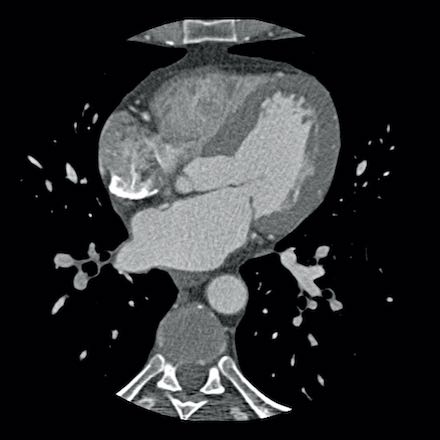

case 3 – Calcium score 0 and severe stenoses.

First, scroll through the CTA images.

How would you describe the findings on the coronary CTA?

The findings are:

- The total calcium

score of 0 indicates the absence of calcified plaque in the coronary

tree. - Severe stenosis

(70-99%) in the mid LAD and D2 branch.